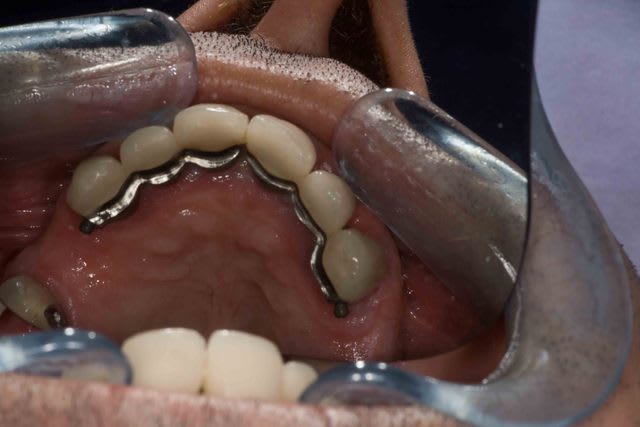

Mais la, apres 1 an de traitements reguliers, entre les lambeaux d'assainissements, les élongations coronaires et les reprises de traitements pourrave j'ai enfin BOUCLE CE CAS !

Concernant les attachements j'ai une preference pour les attachement extra coronaires type VKS . Plusieurs forces differentes, tres facile a changer et pas trop chere. Par contre commme il s'agit d'extracoronaires je solidarise toujours les dents afin de limiter l'effet balancoire sur les couronnes. C'est pour cette raison que sur 45 j'ai mis un crochet et non pas un attachement car la dent est seule.

Pour le reste 11-13 solidarisés, 21 23 solidarisé, 31 unitaires et 32-34 solidarisé.